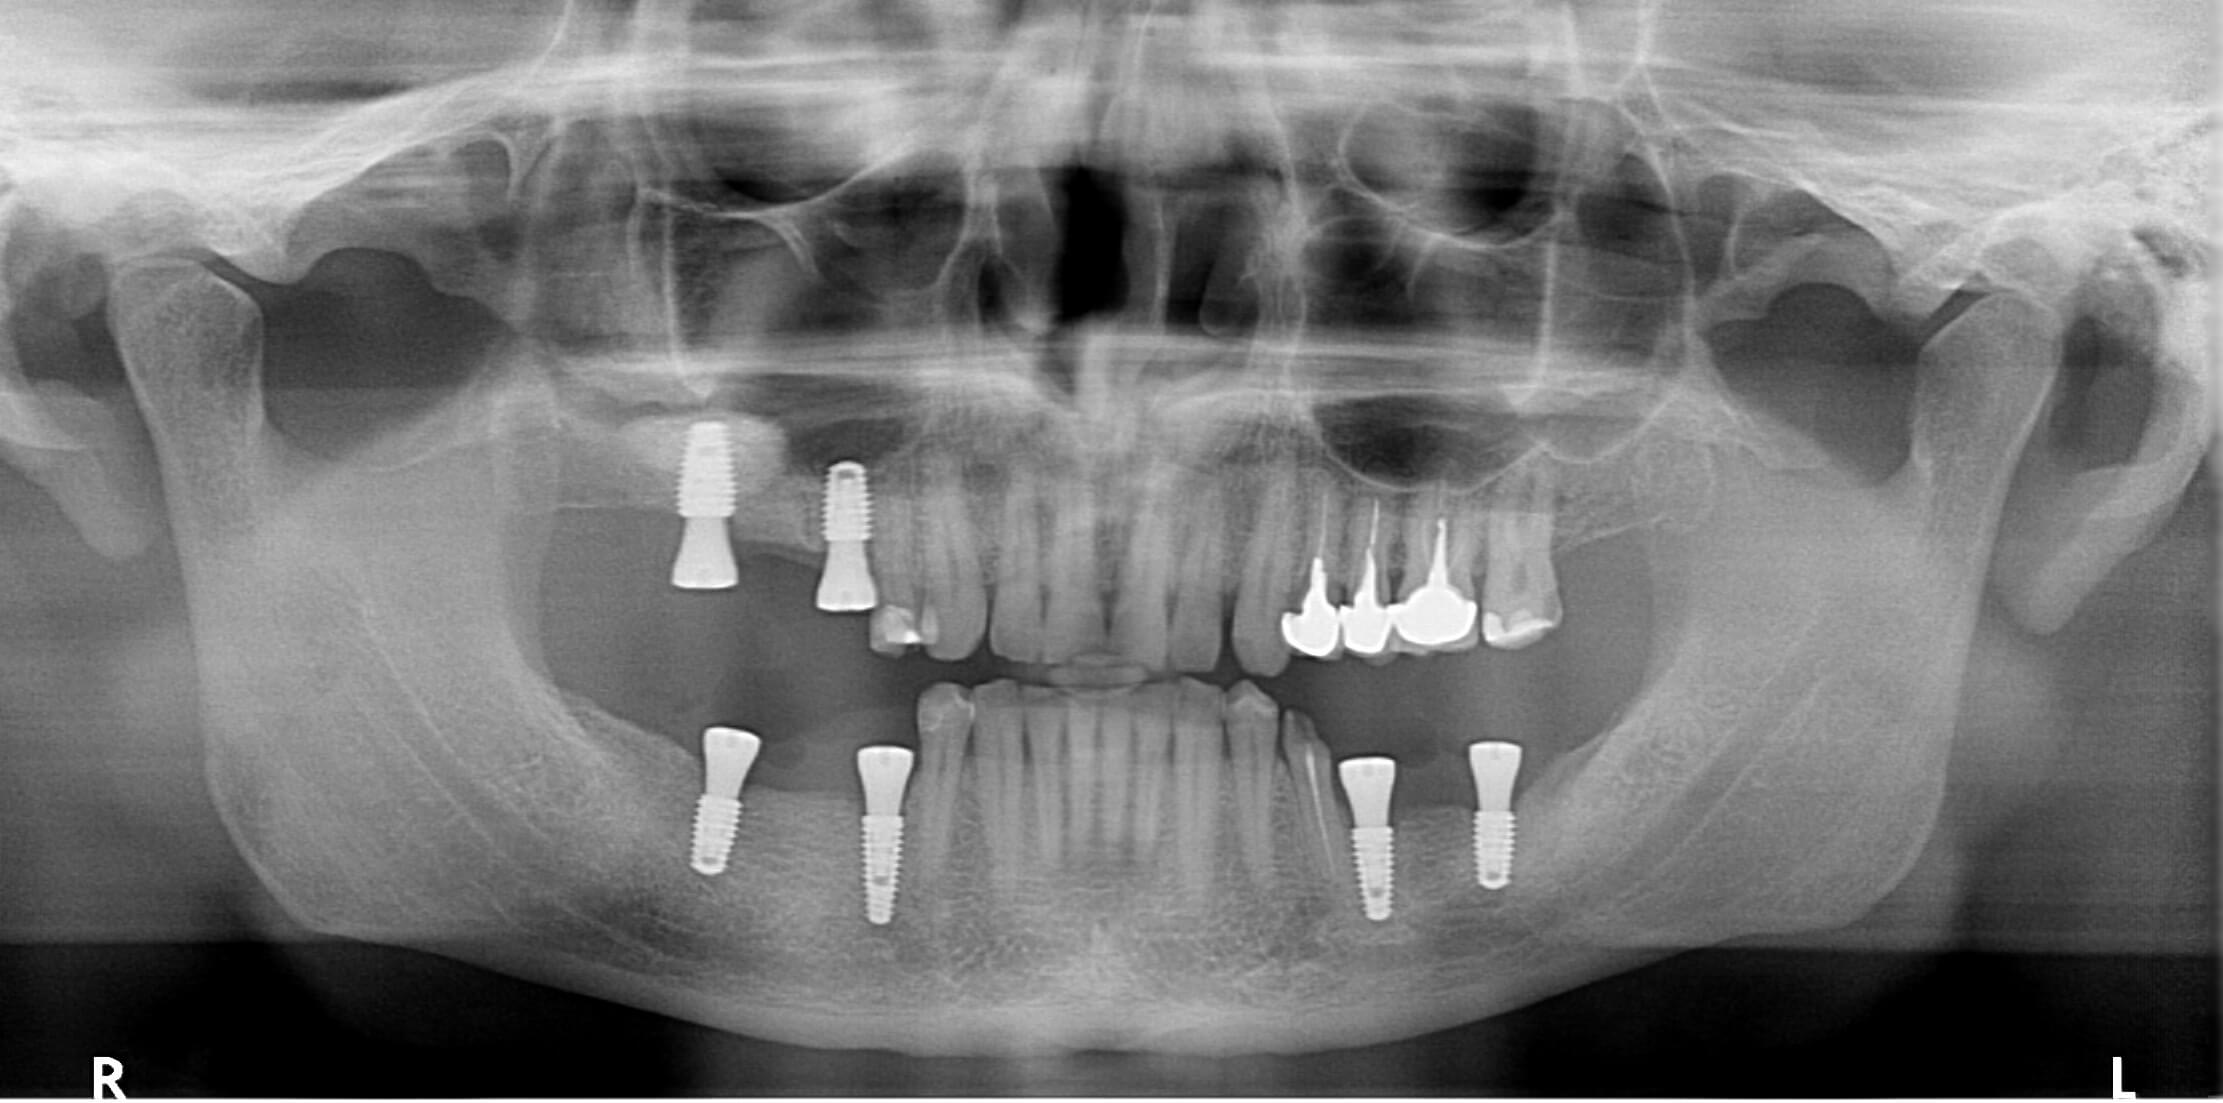

A fairly straightforward, yet still important case for us, involving the rehabilitation of the posterior regions in both jaws. All stages of the treatment can be seen in the photos.

In the first stage, bone grafting (sinus lift) was performed in the upper jaw. At the same time, implants were placed, and soft tissue grafting was carried out.

Exactly four months later, the posterior regions were restored with zirconia crowns and bridge prostheses supported by implants.